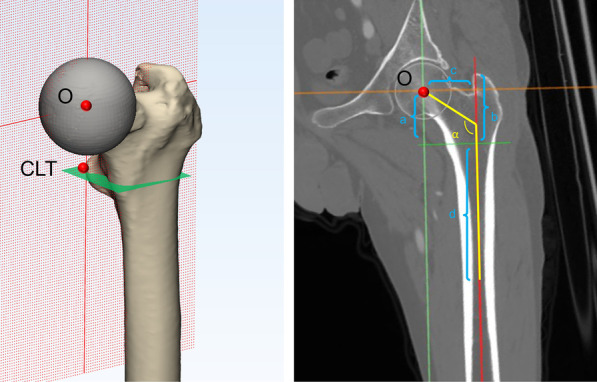

Pelvic CT was performed with a Toshiba brand Aquilion CT scanner (120 kVp, 320 mA, 512 × 512 matrix; slice thickness 0.5 mm) at the Guangdong Provincial People’s Hospital. The patients were placed in a neutral supine position with the patellae facing the ceiling. Scanning was performed from the iliac crest to the complete femoral condyles. All standard CT slices were saved in digital imaging and communications in medicine (DICOM) format and imported into Mimics 19.0 software (Materialise, Leuven, Belgium) for 3D reconstruction. Accordingly, the 3D, coronal, sagittal and transverse views were presented simultaneously in Mimics software. First, the center of the femoral head was established based on the fitting sphere of femoral head. Second, the center of the lesser trochanter (CLT) is the most prominent point on the lesser trochanter on the 3D model. The central axis of the femoral medullary canal was defined as the line between the geometric centers of the medullary canal at the level of 20 mm below the CLT and isthmus of the femur. Thus, the coronal femoral plane was determined by the femoral head center and the central axis of the femoral medullary (Fig. 2A).

Fig. 2.

3D model and the coronal femoral plane of the proximal femur of DDH. O: femoral head center; CLT: center of the lesser trochanter; a: height of FH; b: height of GT; c: femoral offset; d: height of isthmus; ɑ: neck-shaft angle; GT = greater trochanter, FH = femoral head

Based on the coronal plane, the 3D model and CT images were reoriented and the following morphological evaluations included (Fig. 2B): (1) Height of the femoral head (FH): the vertical distance between the femoral head center and level of CLT. (2) Height of the greater trochanter (GT): the vertical distance between the tip of the greater trochanter and the level of CLT. (3) GT–FH height discrepancy. (4) Height of the isthmus: the vertical distance between the level of isthmus and CLT. (5) Neck-shaft angle: the femoral neck axis was first defined by connecting the femoral head center and the midpoint of the narrowest part of the femoral neck; the neck-shaft angle was defined as the angle between the femoral neck axis and the central axis of the femoral medullary canal. (6) Femoral offset: the horizontal distance between the femoral head center and the central axis of the femoral medullary canal. (7) Anteversion of the femoral neck: the angle between the post-condylar line and the projection of the femoral neck axis on the axial plane.